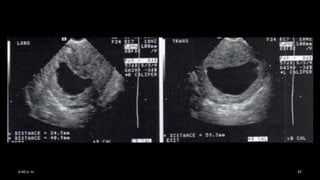

ULTRASONIDO EN EL PRIMER TRIMESTRE DEL EMBARAZO

SACO GESTACIONAL 1 mm

MEDICIÓN DE DIAMETRO MEDIO

Saco gestacional

Primera estructura que se visualiza.

• 4.5 semanas endovaginal

• 5 semanas suprapúbico

• Tamaño de 2 a 3 mm con transductores de 5MHz (4 SDG).

• US: colección de líquido pequeña y redonda rodeada por halo

hiperecogénico.

• diámetro medio del saco

• DMS: L + T + AP /3

Medición del diámetro medio del saco gestacional para cálculo de la edad gestacional

siempre y cuando no se observe el embrión Exactitud de 3-5 días.